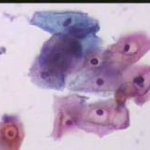

Κυτταρολογικές εικόνες προσβολής του τραχήλου της μήτρας από ιούς κονδυλωμάτων:

Κυτταρολογικές εικόνες προσβολής του τραχήλου της μήτρας από ιούς κονδυλωμάτων: Ασθενής 23 ετών, υποτροπές κολπίτιδος εναλλασσόμενης αιτιολογίας (κολπίτις μικροβιακής αιτιολογίας, κολπίτις από Candida albicans). Τώρα: pH 5, Στο νωπό παρασκεύασμα αρραιή μικροβιακή χλωρίδα. Κολποσκοπικώς επίπεδο μωσαϊκό στο πρόσθιο χείλος. Κοιλοκυττάρωση σε επιφανειακά και διάμεσα κύτταρα. Στην μικροβιοψία τραχηλίτις, υπόνοια για HPV.